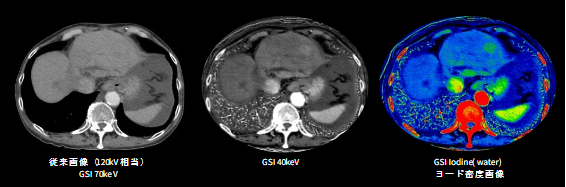

本製品では、従来のCT検査において主目的とされている形態評価にとどまらず、目的部位の機能情報の提供を実現しています。本製品では160mmカバレッジ、且つ最大1300mAが出力可能な次世代型Intelligent X線管球を搭載しており、電子ビームをmsec単位で集束・制御することで、管電圧ならびに管電流を変調させながら2つの異なるエネルギーデータを取得する(Synchronized kV/mA switching GSI)ことが可能です。

高エネルギーデータと低エネルギーデータをシグナルレベルで最適化させることで、低keV画像やヨード密度画像等MD画像の更なる高画質・高精度化を実現。低keV画像やヨード密度画像は、コントラストの向上が可能であるため、腫瘍の正確な描出、診断確信度の向上が期待でき、また従来CTでは得られなかった定量評価、付加価値の高い機能情報の提供を可能とします。

※ビュー毎の管電圧のスイッチングに合わせて管電流も変調させるSynchronized kV/mA switching GSIの概念図

※GSIでのヨードコントラスト強調画像による病変・関心部の描出能向上画像